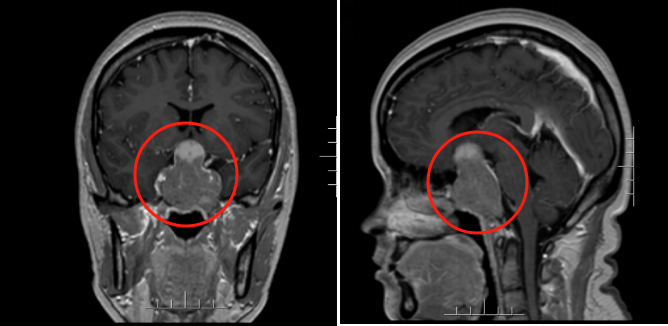

该院神经外三科主任金鑫接诊了阿婷,根据影像资料和症状,初步怀疑阿婷患有垂体瘤合并卒中,“肿瘤最长直径超过5厘米,对患者的内分泌功能和视力都造成了影响”。

术前影像资料

8月26日,该院神经外三科团队为患者行神经内镜下经鼻蝶肿瘤切除术,成功将大小约4.4厘米×3.5厘米×5.1厘米的肿瘤切除。术后病理诊断为垂体腺瘤。